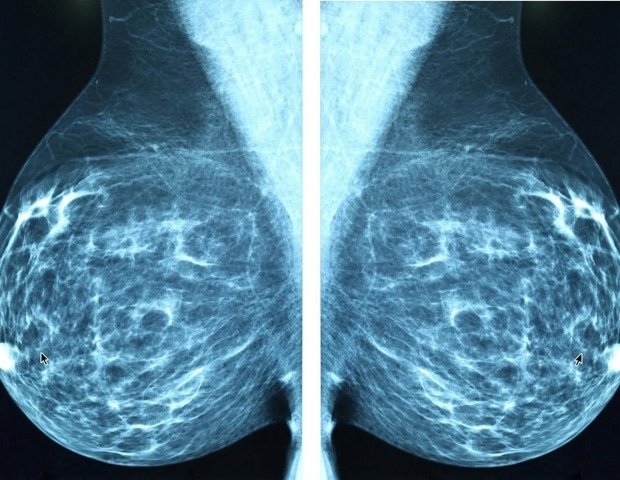

The study, commissioned by The Ohio State University Comprehensive Cancer Center – Arthur G. James Cancer Hospital and Richard J. Solove Institute (OSUCCC – James), found that 44% of women incorrectly believe that mammography should begin annually at age 50. Leading medical organizations recommend that women at average risk for breast cancer begin having annual mammograms starting at age 40.

Confusion continues even after the US Preventive Services Task Force (USPSTF) updated its mammography recommendations in April 2024. The task force recommends that women at average risk get a mammogram every other year starting at age 40. However, many medical experts, including the Society of Breast Imaging and the American College of Radiology, continue to recommend that average-risk women be screened annually starting at age 40, a guideline that the OSUCCC (James) also follows.

In April 2026, the American College of Physicians updated its guidance to recommend that average-risk women ages 50 to 74 receive a mammogram every two years, citing individualized decision-making. OSUCCC – James follows radiology-focused guidelines that recommend starting annual mammograms starting at age 40. Under the Affordable Care Act, annual mammogram screenings starting at age 40 are covered by Medicare and most private insurance companies. Insurance coverage may vary. Patients should check with their insurance company for specific coverage.